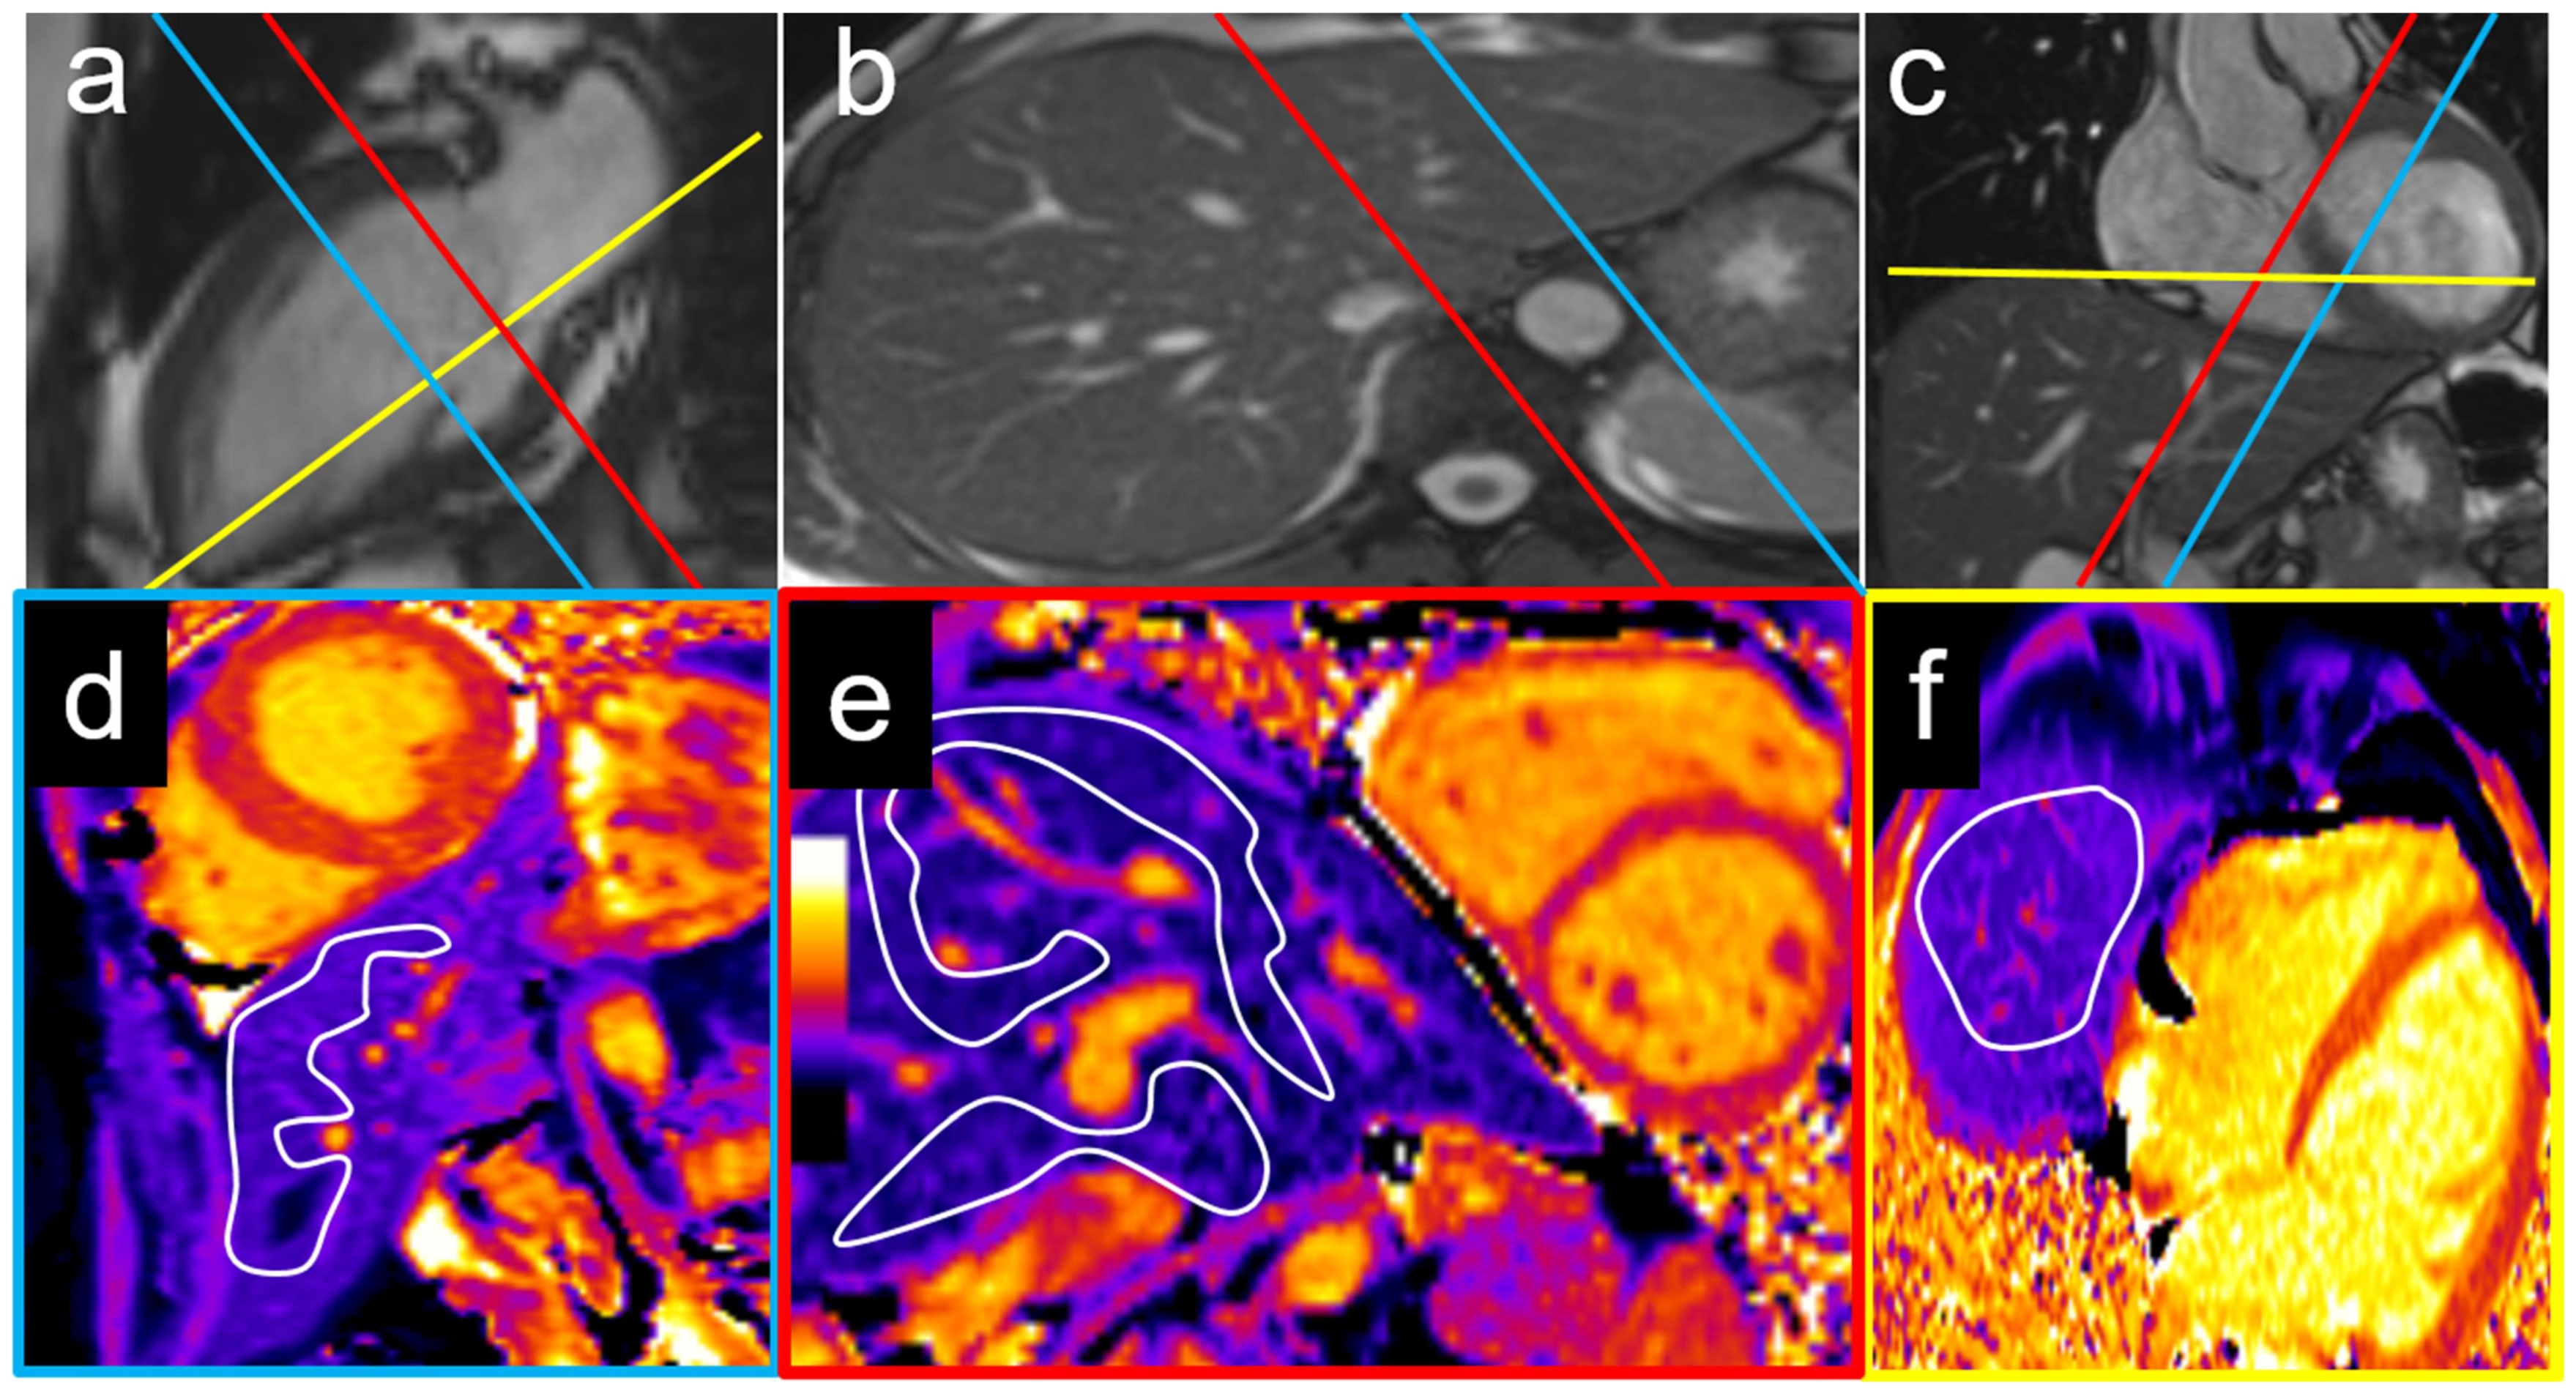

2.3. Cardiac Magnetic Resonance Imaging Protocol

2.5. Cardiac MRI Analysis